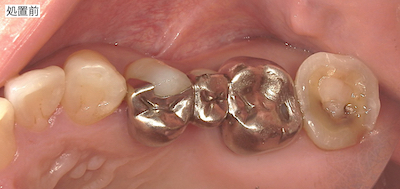

銀歯を白くしたいと患者さんがご来院されました。

治療前後の比較です。